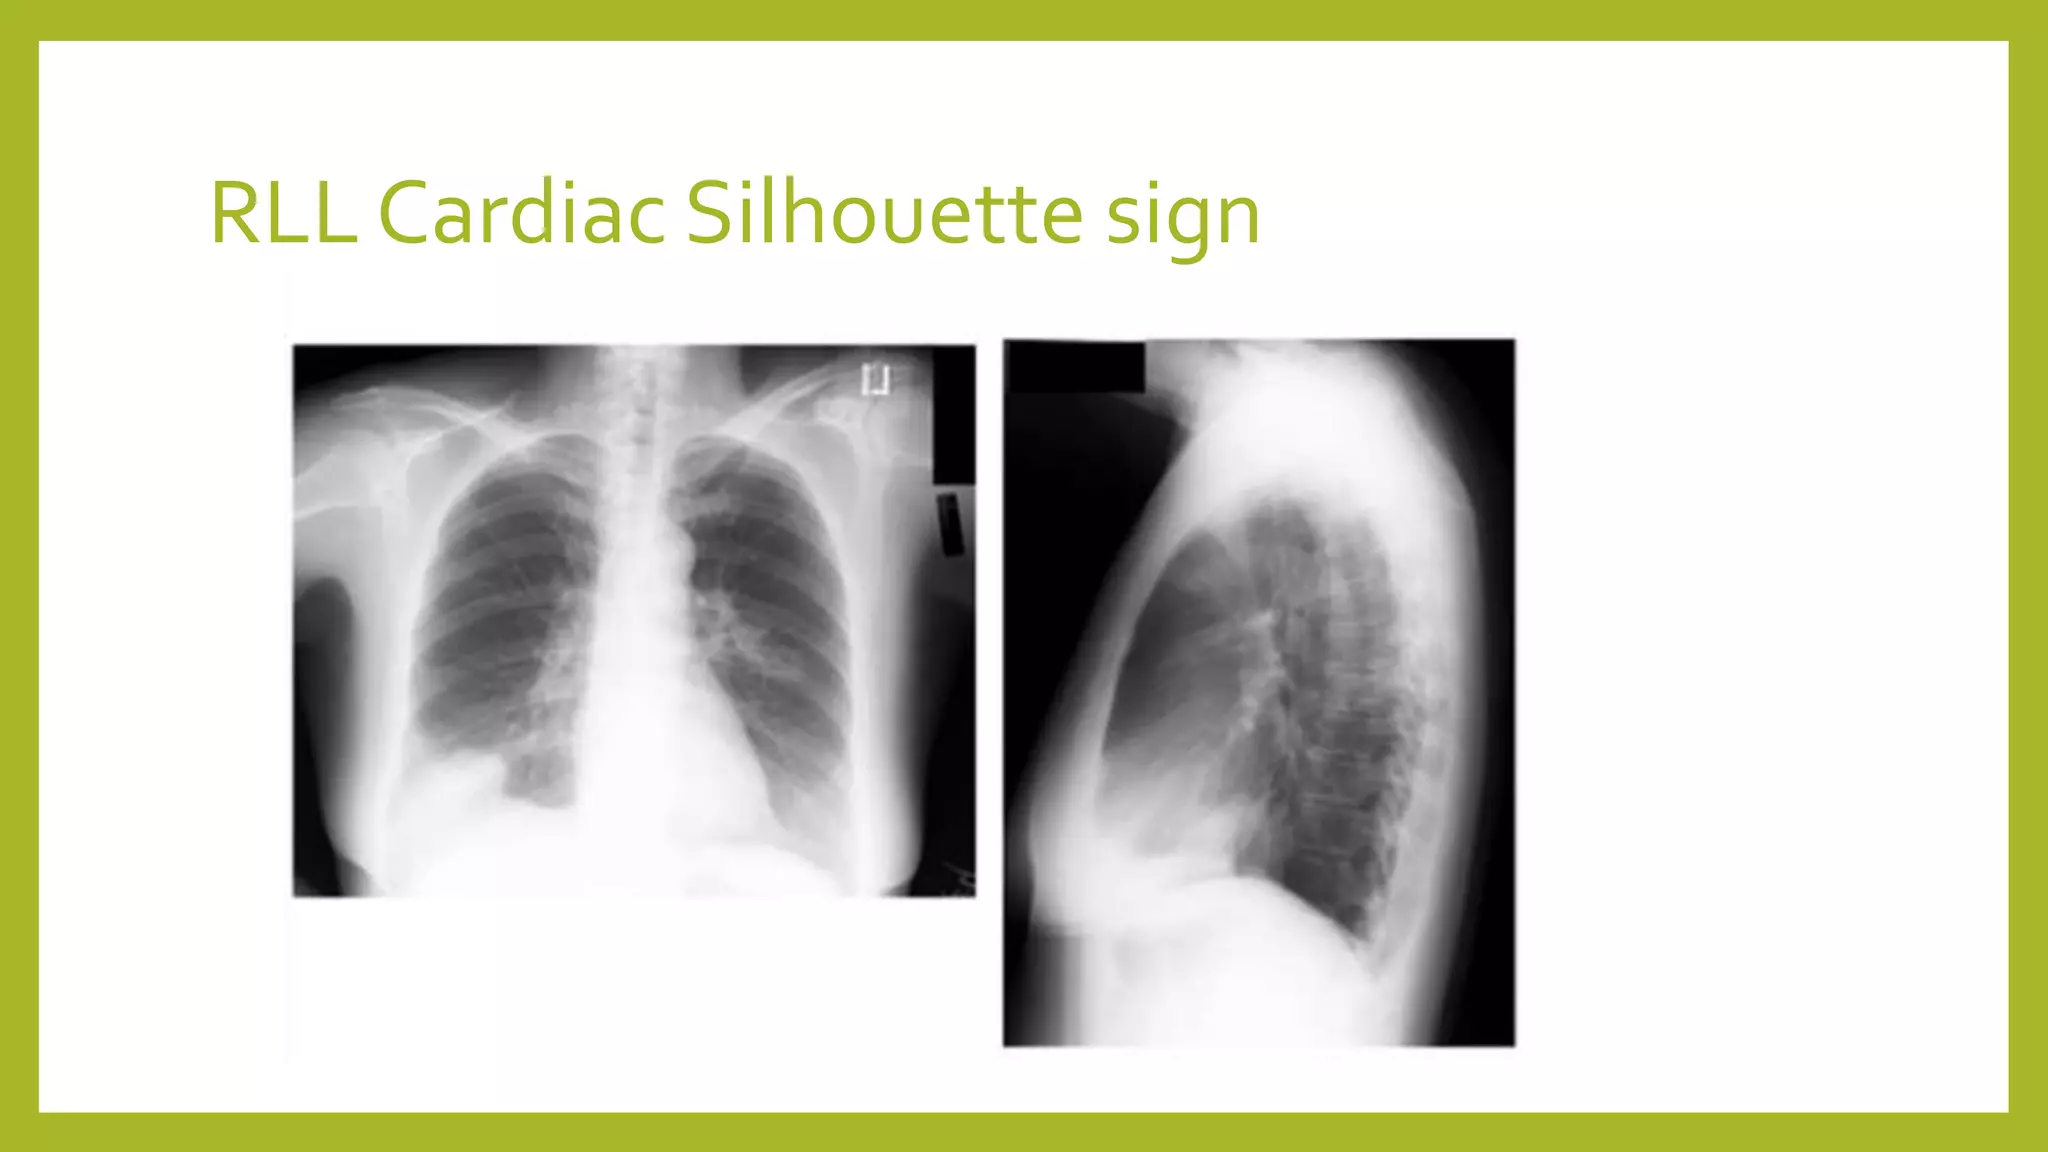

The document provides guidance on approaching and interpreting chest x-rays (CXR). It outlines steps to check the name, date and quality of the film, systematically scan the CXR looking for abnormalities, and determine if the lungs appear too white or black. Specific signs are described to help localize abnormalities, including the cardiac silhouette sign and pleural effusion signs. Examples are given of respiratory distress syndrome, tetralogy of fallot, transposition of great arteries, and total anomalous pulmonary venous return. The take home message is to summarize positive findings, compare to prior CXRs if available, and confirm findings with a radiologist.